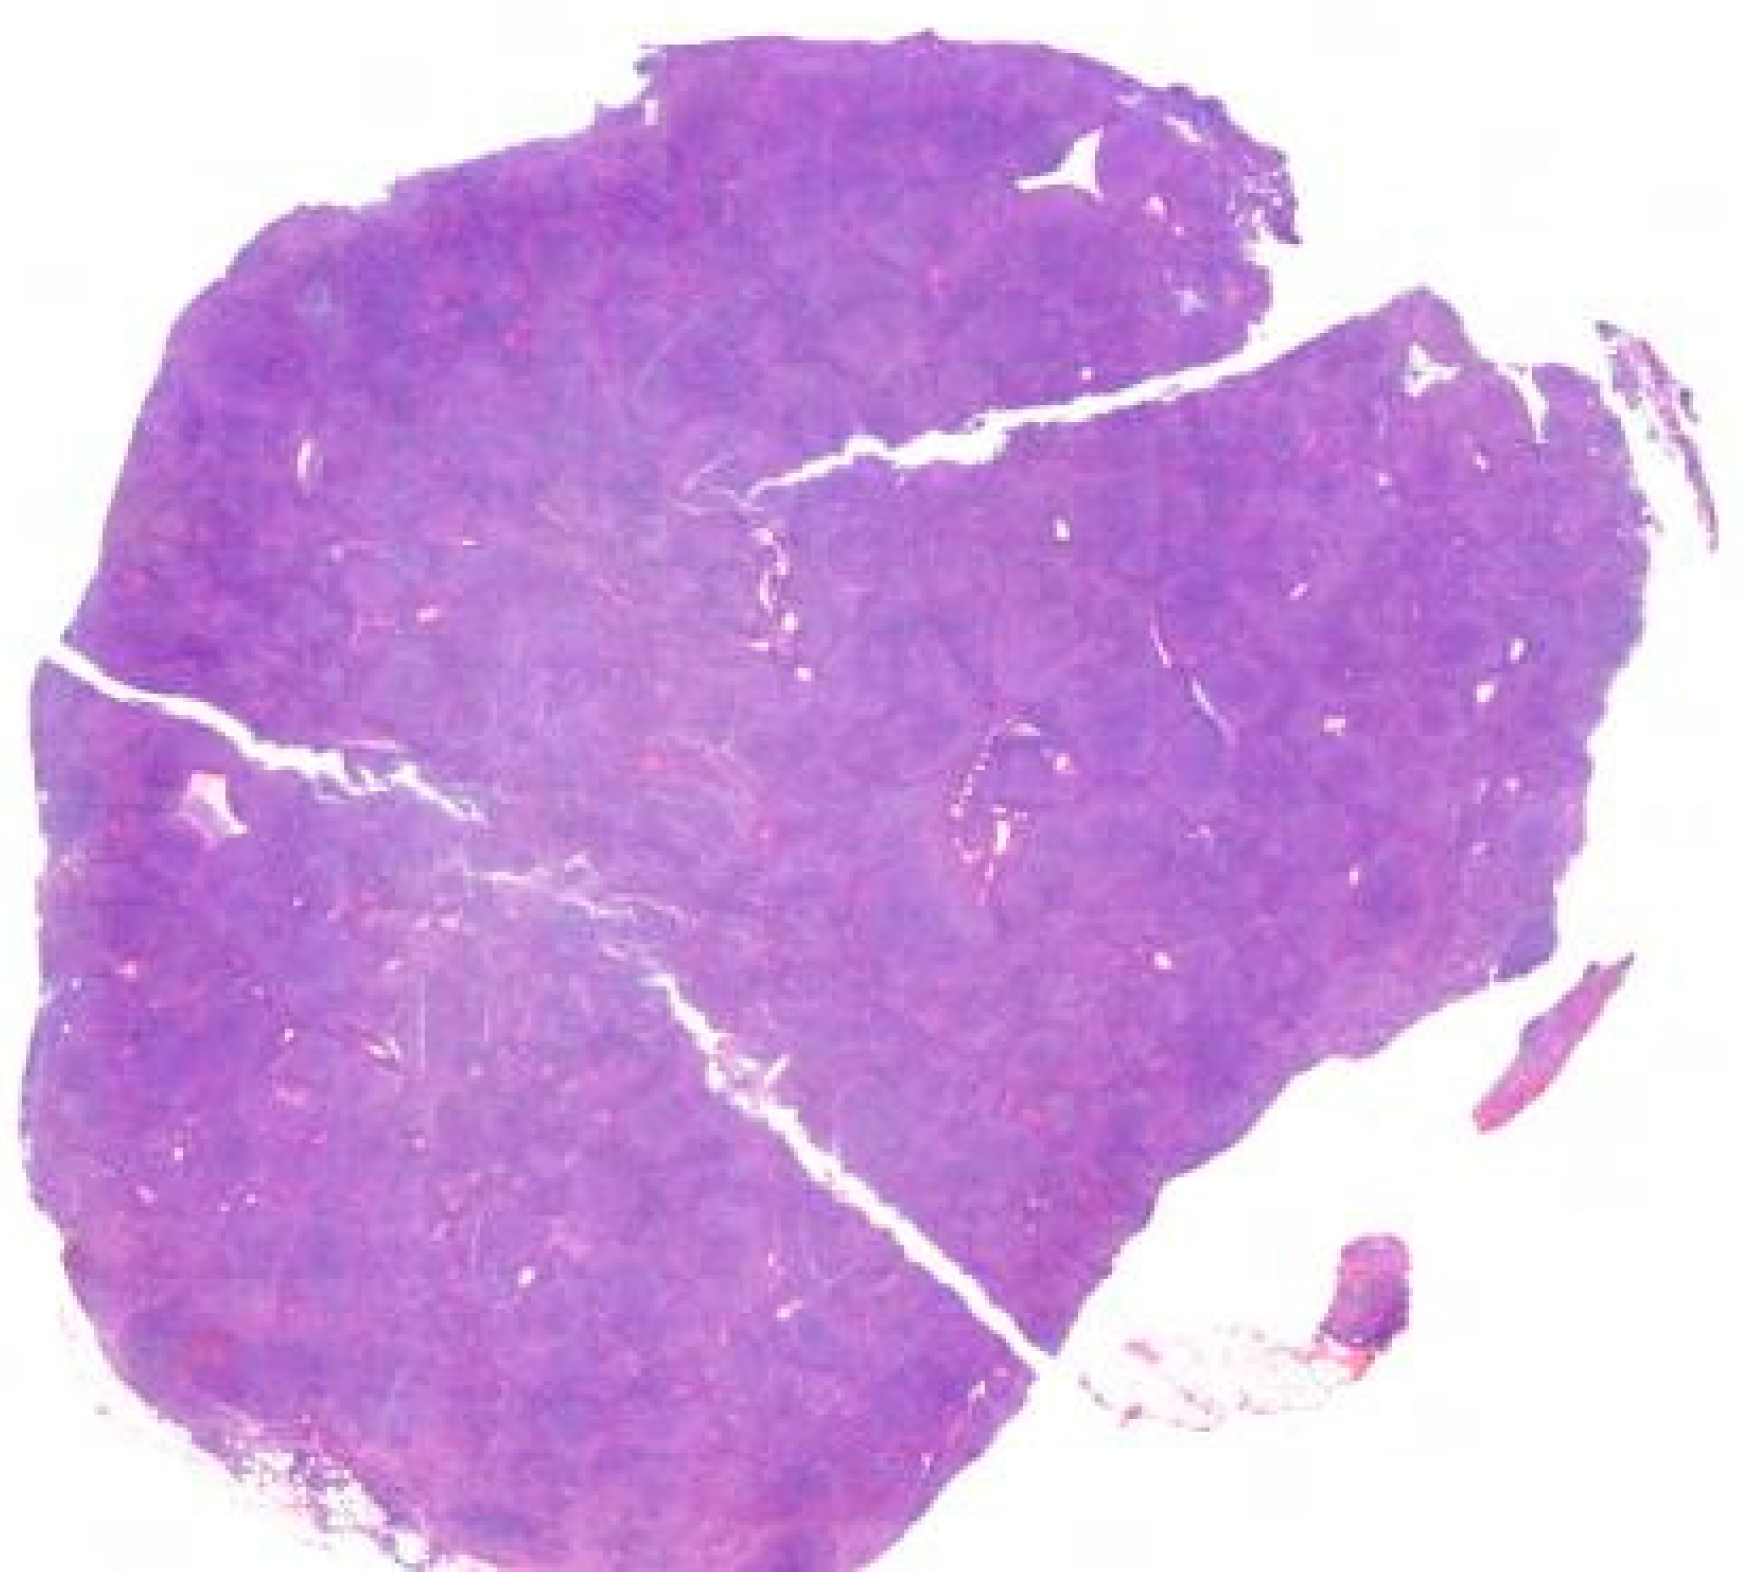

Figure 5.

The lymph node architecture is completely effaced by a rather monotonous small-cell lymphoid population with a regular nuclear outline.